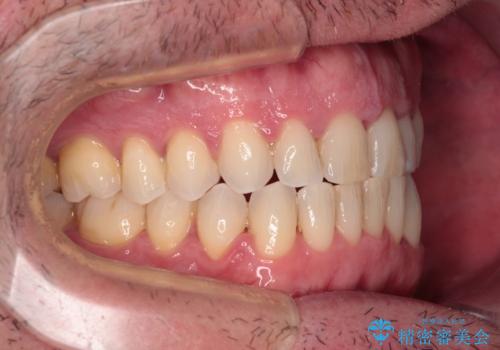

舌のトレーニング自体は簡単なものですが、無意識下でも舌が突出しないようにしなければならないため、毎日継続することが最大の難関です。

時間はかかりましたがトレーニングを頑張ってくださり、無事に前歯を接触させることができました。